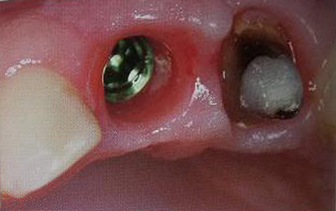

Implantele dentare reprezinta la ora actuala singura posibilitate de a inlocui dintii lipsa prin protezare fixa rezultand o dentitie foarte apropiata de dintii naturali. Implantele dentare sunt niste radacini artificiale realizate din titan care se insera in os. Dupa o perioada de aproximativ 6 luni perioada necesara pentru integrarea implantului, acestuia i se ataseaza un bont protetic pe care ulterior se fixeaza coronita de ceramica sau proteza.